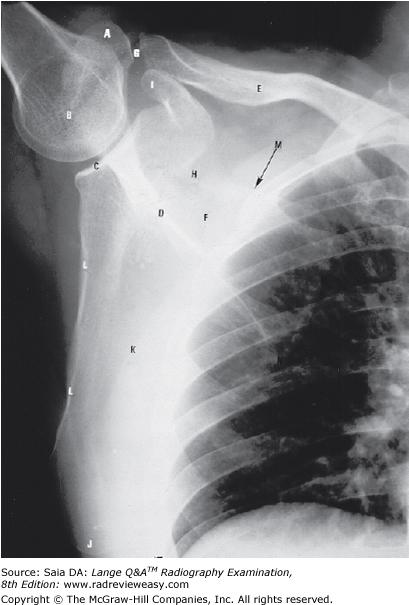

The scapula shown in Figure 2–29 demonstrates

- its posterior aspect

- its costal surface

- its sternal articular surface

1 only

In Figure 2–29, which of the following is represented by the number 3?

Acromion process

Which of the following indicates the scapular costal surface seen in the figure below?

K

In Figure 2–29, which of the following is represented by the number 7?

A Medial border B Lateral border C Inferior angle D Superior angle

Lateral border